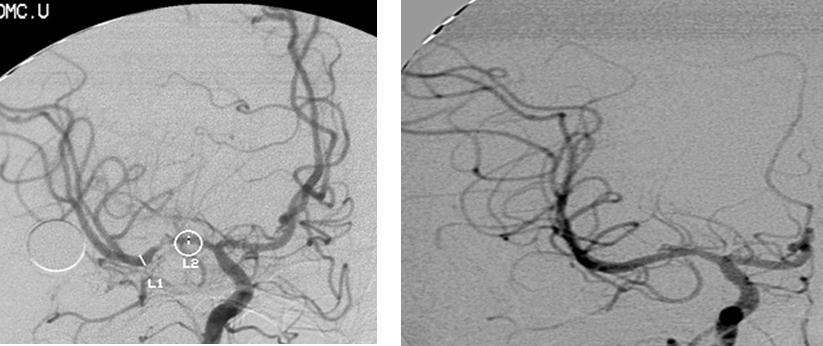

A twenty-nine-year-old female was admitted in Feb, 2006 because of episodic left limb numbness and weakness for half a year. The duration of the episode lasted for a few minutes, seldom over ten minutes. There was an attack every several days. She denied special medical history. She did not live in the pandemic area of Leptospirosis. Her blood pressure was 110/65mmHg and body weight was 51 kilograms. Physical examination found no abnormality. Magnetic resonance angiogram (MRA) (Feb 22) showed severe stenosis in the M1 segment of right MCA. In the source images of MRA, an oval area of abnormal signal in the right basal ganglion was found (Figure 1). Blood routines, coagulation tests, blood biochemistry tests, and C-reactive protein level were normal. The anti-nuclear antibody (ANA), anti-extractable nuclear antigen (ENA) antibodies, and anti-neutrophil cytoplasmic antibodies (ANCA) were negative. Serologic test for Syphilis was negative. Blood sedimentation rate (ESR) was 20 mm/h, and the level of anti-streptolysin O microtitration test (ASO) was 395 IU/ml (0-200 IU/ml). Digital subtraction angiography (DSA) detected severe stenosis (95%) in M1 segment of the right MCA, and the distal blood flow was compromised (Figure 2). The patient was given aspirin 100mg/d, clopidogrel 75mg/d and atorvastatin 20mg/d since Feb 26. Due to the finding of high ASO level, she was given penicillin (4 million IU, bid) for a week. Because of disagreement between the consulting physician and the interventional radiologist, her angioplasty and stenting was delayed till Mar 21 on her request. During the waiting time, her attacks did not reduce. Before the operation, besides the combination of aspirin and clopidogrel, subcutaneous low molecular weight heparin (LMWH) (5000U, q12h) was given for 5 days. After a complete diagnostic evaluation of the blood vessels with DSA, stenting was performed with a stainless steel stent 2.75 mm in diameter by 1.5 cm in length (PC, Abott Company) at the presure of 7 atm. No compromise of perforating branches was found and residual stenosis was less than ten percent on angiography (Figure 2).

Figure 2.Right MCA before and after angioplasty and stenting

The right MCA stenosis, which led to the transient ischemic attack (TIA) symptoms, was definitely diagnosed. Angioplasty and stenting was conducted after full preparation of dual anti-platelet therapy. Immediately before the operation, LMWH was used in combination and was continued after operation. Her condition was stable in the first two days after operation. Then crescendo TIA recurred and led to motor impairment. Two lesions were shown in the emergent CT images. One was near the anterior horn of the right lateral ventricle, by which it was difficult to explain the symptoms and physical signs. The other was in basal ganglia, and was related to the symptoms and signs. The signal in this region had been slightly higher than the counterpart in the left in the source image of MRA before operation. Hence the lesion in basal ganglia was thought to result from hemodynamic impairment in distal parts of stenotic MCA. Both lesions had clear boundaries, which indicated that the infarction in the area supplied by deep branch of MCA occurred before the TIA attacks. The crescendo TIA worsened gradually, but got partial recovery after volume expansion treatment initially. TCD test showed the blood flow velocity increased in both ACA, especially in the right, while that in the right MCA did not significantly increase. This indicated that some collateral circulation had formed, to counteract hypoperfusion caused by progressive stenosis in the right MCA. Based on these, we deduced that there was IST which did not completely block the right MCA. The symptoms and physical signs appeared again when there was failure of collateral compensation. Because there were new lesions on CT scan and the patient had been treated with dual anti-platelet treatment and anticoagulation, thrombolytic therapy could not be given. So we gave unfractionated heparin (UFH). The symptoms and physical signs disappeared on the next day. But two days later during the same treatment, the symptoms and signs recurred, volume expansion was ineffective, this indicated that initial recovery of symptoms was due to compensatory collateral circulation, and anticoagulation therapy with UFH may also play a role. But this could not prevent thrombosis from progressing, so we increased the dose of anticoagulation drugs, the symptoms and signs disappeared eventually. CTA (Apr 3) and repeated TCD (Apr 17) confirmed our reasoning with attenuated proximal lumen of right MCA and increased blood flow velocities of the right MCA and ICA.